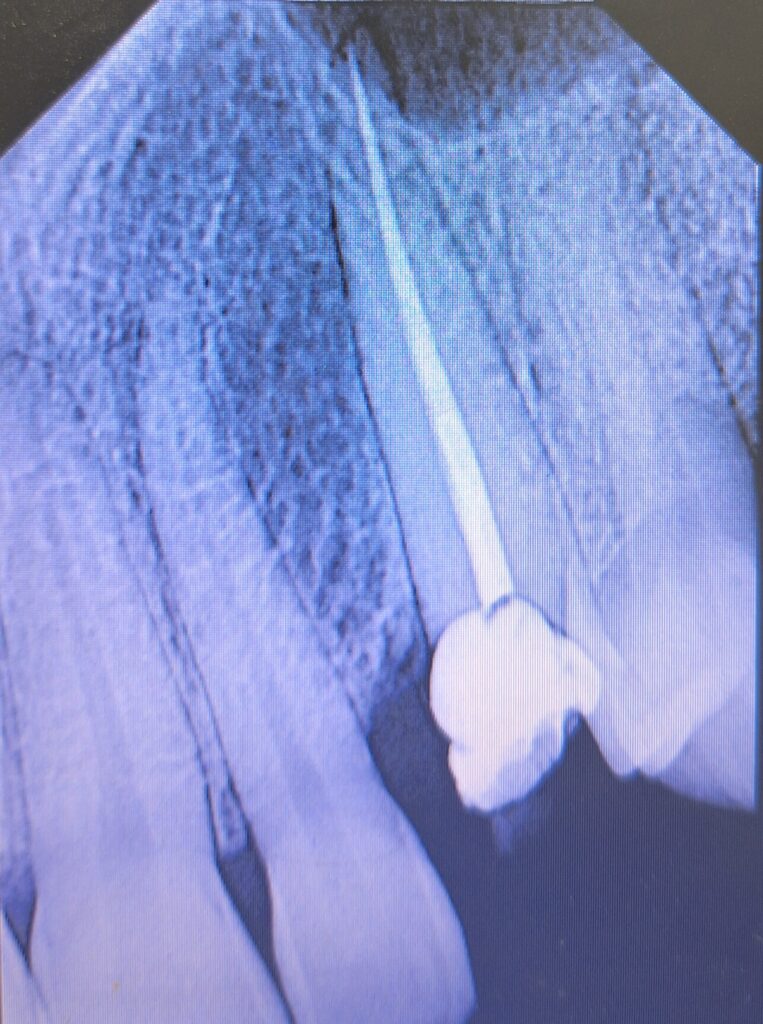

Veja alguns de meus casos